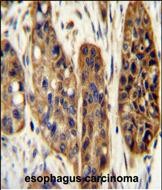

IHC 1/100-1/500 Human,Mouse,Rat